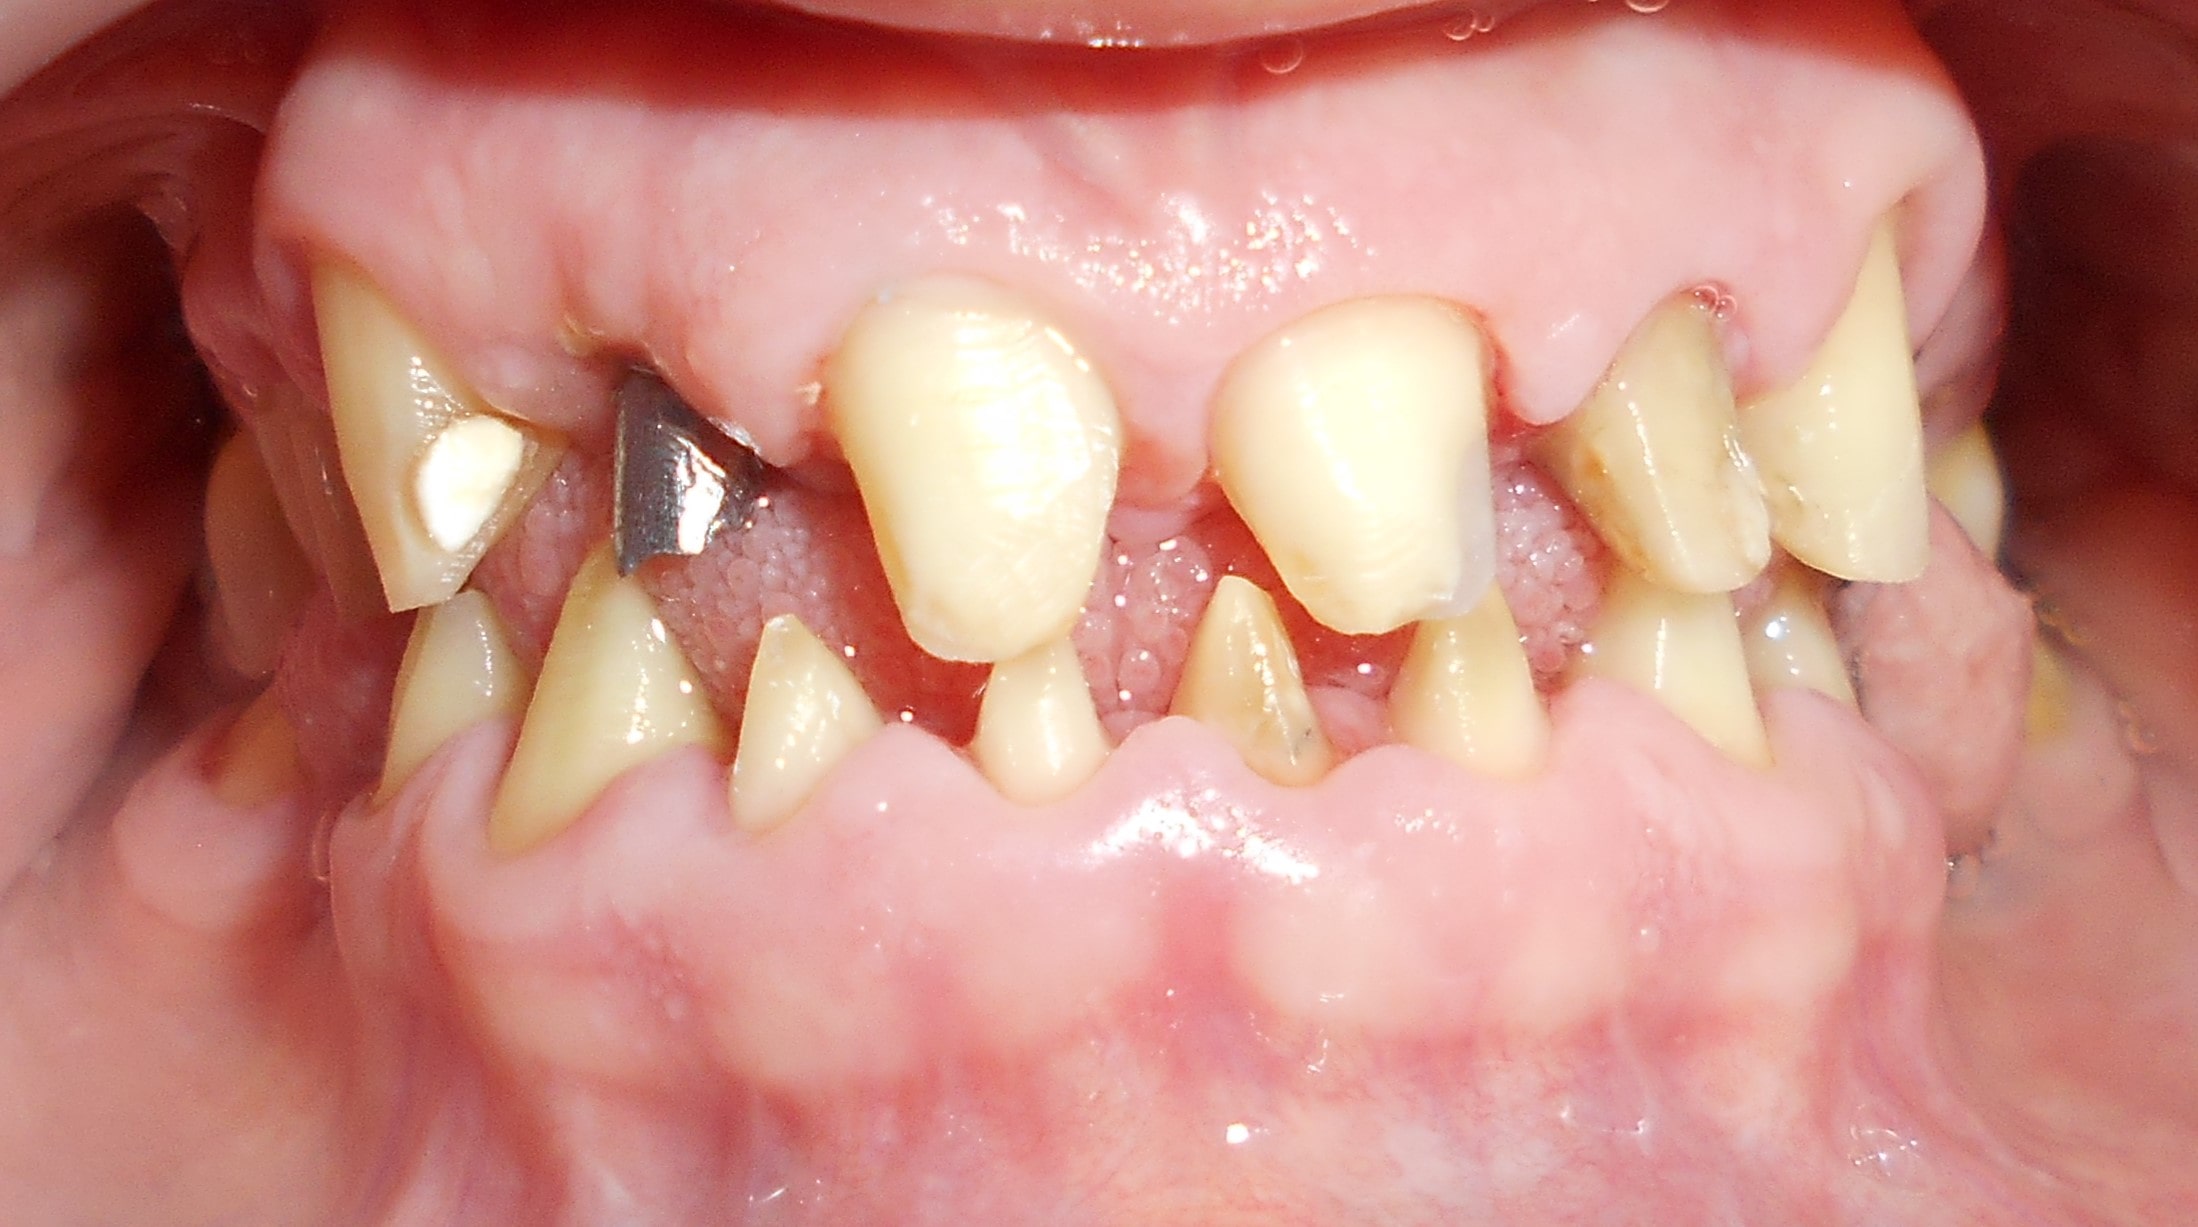

Pacijent 3

Pacijent dolazi sa starim mostovima i izraženom parodontopatijom u donjoj vilici. Urađeno je skidanje postojećih mostova i istovremena ekstrakcija svih parodontopatičhin zuba uz ugradnju sedam implantata u gornjoj vilici i pet implantata u donjoj vilici. Pacijent je nakon tri dana bio privremneo protetski zbrinut sa fiksnim privremeni krunicama koje su fiksirane na tek ugrađenim implantaima. Nakon četiri meseca je izrađen fiksni cirkonijum kermički- bezmetalni most u gornjoj i donjoj vilici. Rad uspešno završen pre tri godine.